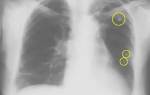

1. Единичные участки уплотнений (визуализируются от 2 до 6) могут быть признаком злокачественной опухоли или представлять собой типичные возрастные изменения в легких (как правило, фиброзного характера).

2. Множественные очаги чаще всего оказываются симптомами пневмонии или туберкулеза. Однако в редких случаях очаги в количестве более шести могут означать развитие онкологии.